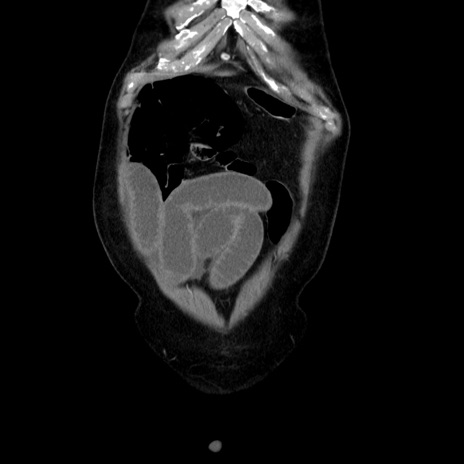

症例30(冠状断像)

【症例】80歳代男性

【主訴】臍周囲痛

【現病歴】約6時間前から臍下部痛が出現。次第に腹部膨隆・背部痛も生じてきたため来院。背部痛の場所は変化しない。

【身体所見】意識清明、BT 36.3℃、BP  131/87mmHg、P 87bpm、SpO2 100%(RA)、臍周囲自発痛・圧痛あり、反跳痛なし、自発痛部位に一致して板状硬あり、腹部膨隆、腸雑音減弱、CVA tenderness両側陰性。

【データ】WBC 19600、CRP 0.33